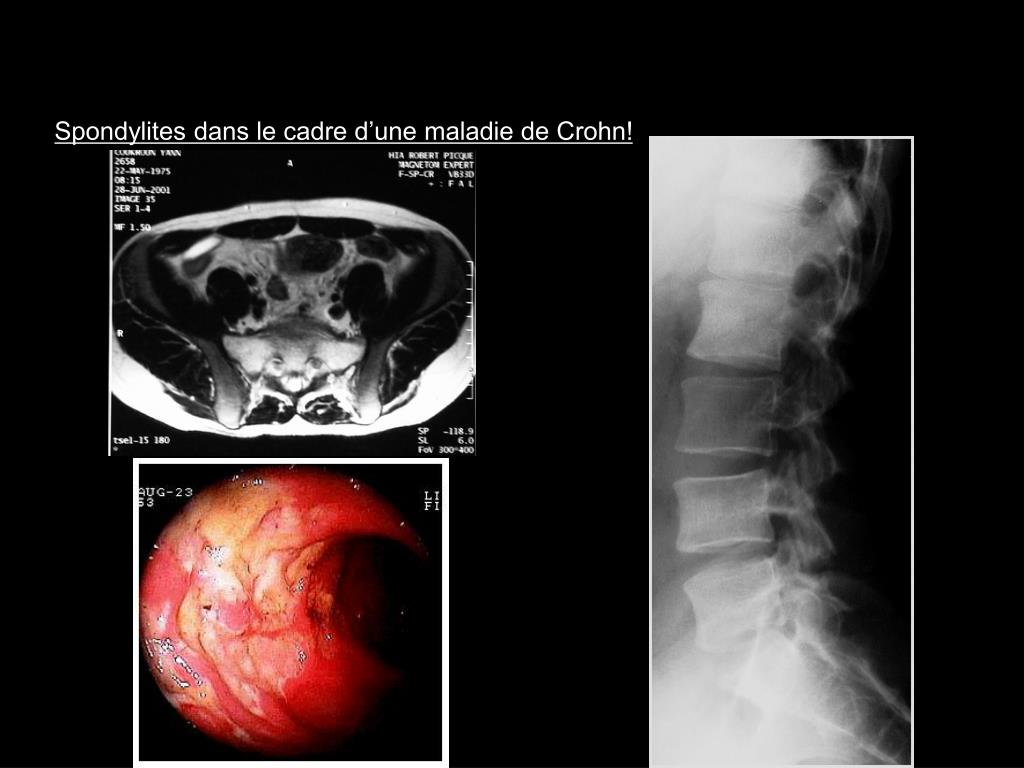

19. Spondylites dans le cadre d’une maladie de Crohn!